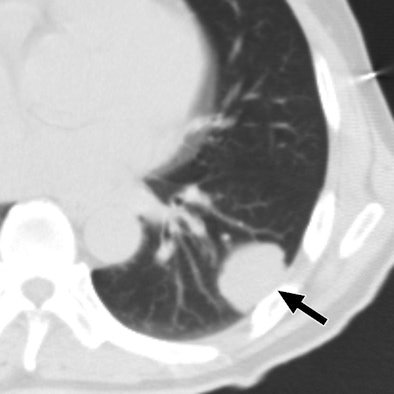

| 47-year-old man with metastatic hepatocellular carcinoma. Above, axial CT scan obtained before tomotherapy shows small well-defined nodule (arrow), target lesion, in right upper lobe. Below, three-month follow-up CT scan reveals focal area of ground-glass attenuation (arrows) around target, representing radiation pneumonitis. All images courtesy of the American College of Radiology. |